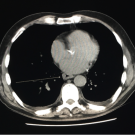

A 53-year-old man presented to the emergency department and was subsequently admitted to the medical ward with hematemesis, melena, and atypical chest pain, all occurring intermittently for the past few...